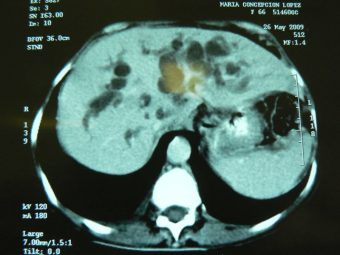

Derivación externa segmento III

Envíado por Dr. Carlos Miguel Zavaleta Consuegra